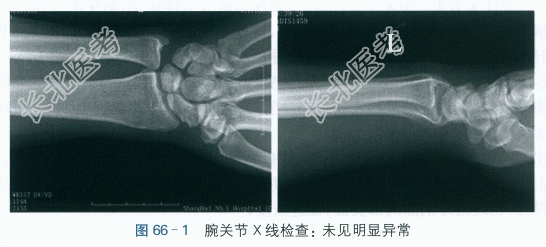

腕关节X线检查,未见明显异常,如图66-1所示。